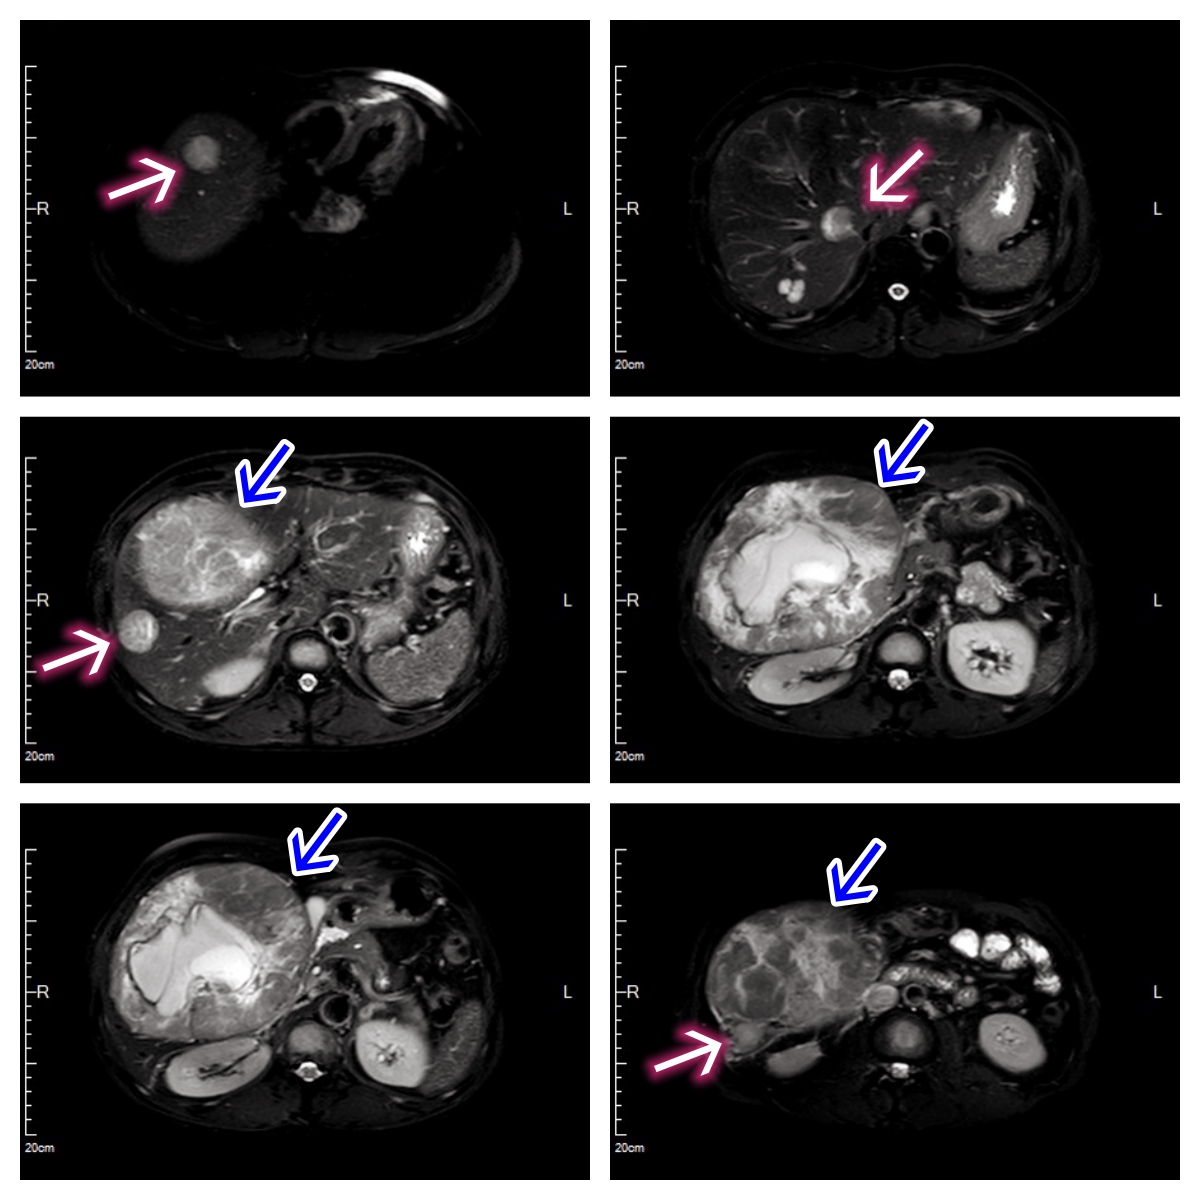

中年男性,右腹部胀痛3月余。MRI检查提示右肝巨块型肝癌并肝内多发子灶(4个),同时合并多发骨转移瘤。临床诊断分期:肝细胞癌(Ⅳ期)

MRI横断面